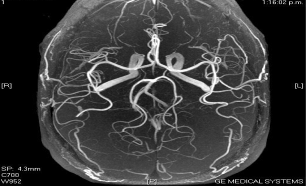

Визуализация без использования контрастного вещества - выполнение визуализации нижних конечностей при высоком разрешении и без использования контрастного вещества и с применением Inhance DeltaFlow, нейровизуализации артерий и вен с применением 3D PC Inhance, количественная визуализация перфузии с применением 3D ASL, а также непрерывная и надежная визуализация при свободном дыхании сети вен и артерий с применением IFIR. Все, без контрастного вещества.

Нервы и сосуды - получение великолепных изображений нервов и сосудов с использованием CUBE, SWAN, PROPELLER, 3D MERGE и других приложений. Радиочастотная технология GEM и 50 см область сканирования позволяет захватить весь позвоночник за два приема.